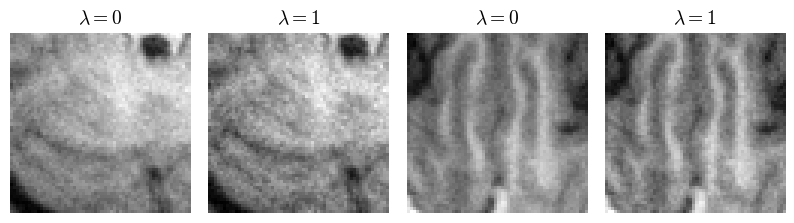

Fig. 5(a) shows representative brain and knee slices for the CS-MRI task, and Fig. 5(b) shows zoomed-in versions of the red arrow regions for the brain slices. We notice a significant visual similarity between the same hyperparameters for Unet and HyperRecon-L models. In general, a higher weight on MAE tends to lead to more blurry and smoother reconstructions, while a higher weight on SSIM tends to lead to more noisy reconstructions with more high frequency content. In addition, MAE tends toward less contrast between hypo-intense and hyper-intense regions, whereas SSIM accentuates this contrast more. With baseline models where 𝝀𝝀\bm{\lambda} must be chosen before training, these variations would be completely missed and end users would be stuck with one reconstruction. Additional slices for CS-MRI, denoising, and superresolution tasks are presented in the Appendix.

Figure 5: (a) Representative slices for SL on CS-MRI task with 8-fold under-sampling. Ground truth and input images are denoted in the first column. Top row are baseline Unet reconstructions with varying λ𝜆\lambda. Bottom row (red) are HyperRecon-L reconstructions with varying λ𝜆\lambda. PSNR values in reconstructions provide a basis of comparison between Unet and HyperRecon-L reconstructions of the same λ𝜆\lambda. Brain slices are cropped to show detail. Arrows indicate corresponding points where the difference between reconstructions can be appreciated. (b) Representative brain patches for HyperRecon-L, centered around red arrows.